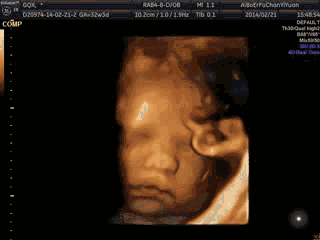

更便捷 | 四维彩超自助下载,永久存储宝宝“0岁”大片

并为Ta留下珍贵的0岁写真相册,

四维彩超适合检查时间为单胎孕22-26周,双胎孕21-23周,此时胎儿器官发育更完善,羊水量足,便于排畸,也易采集到相对清晰的图像。